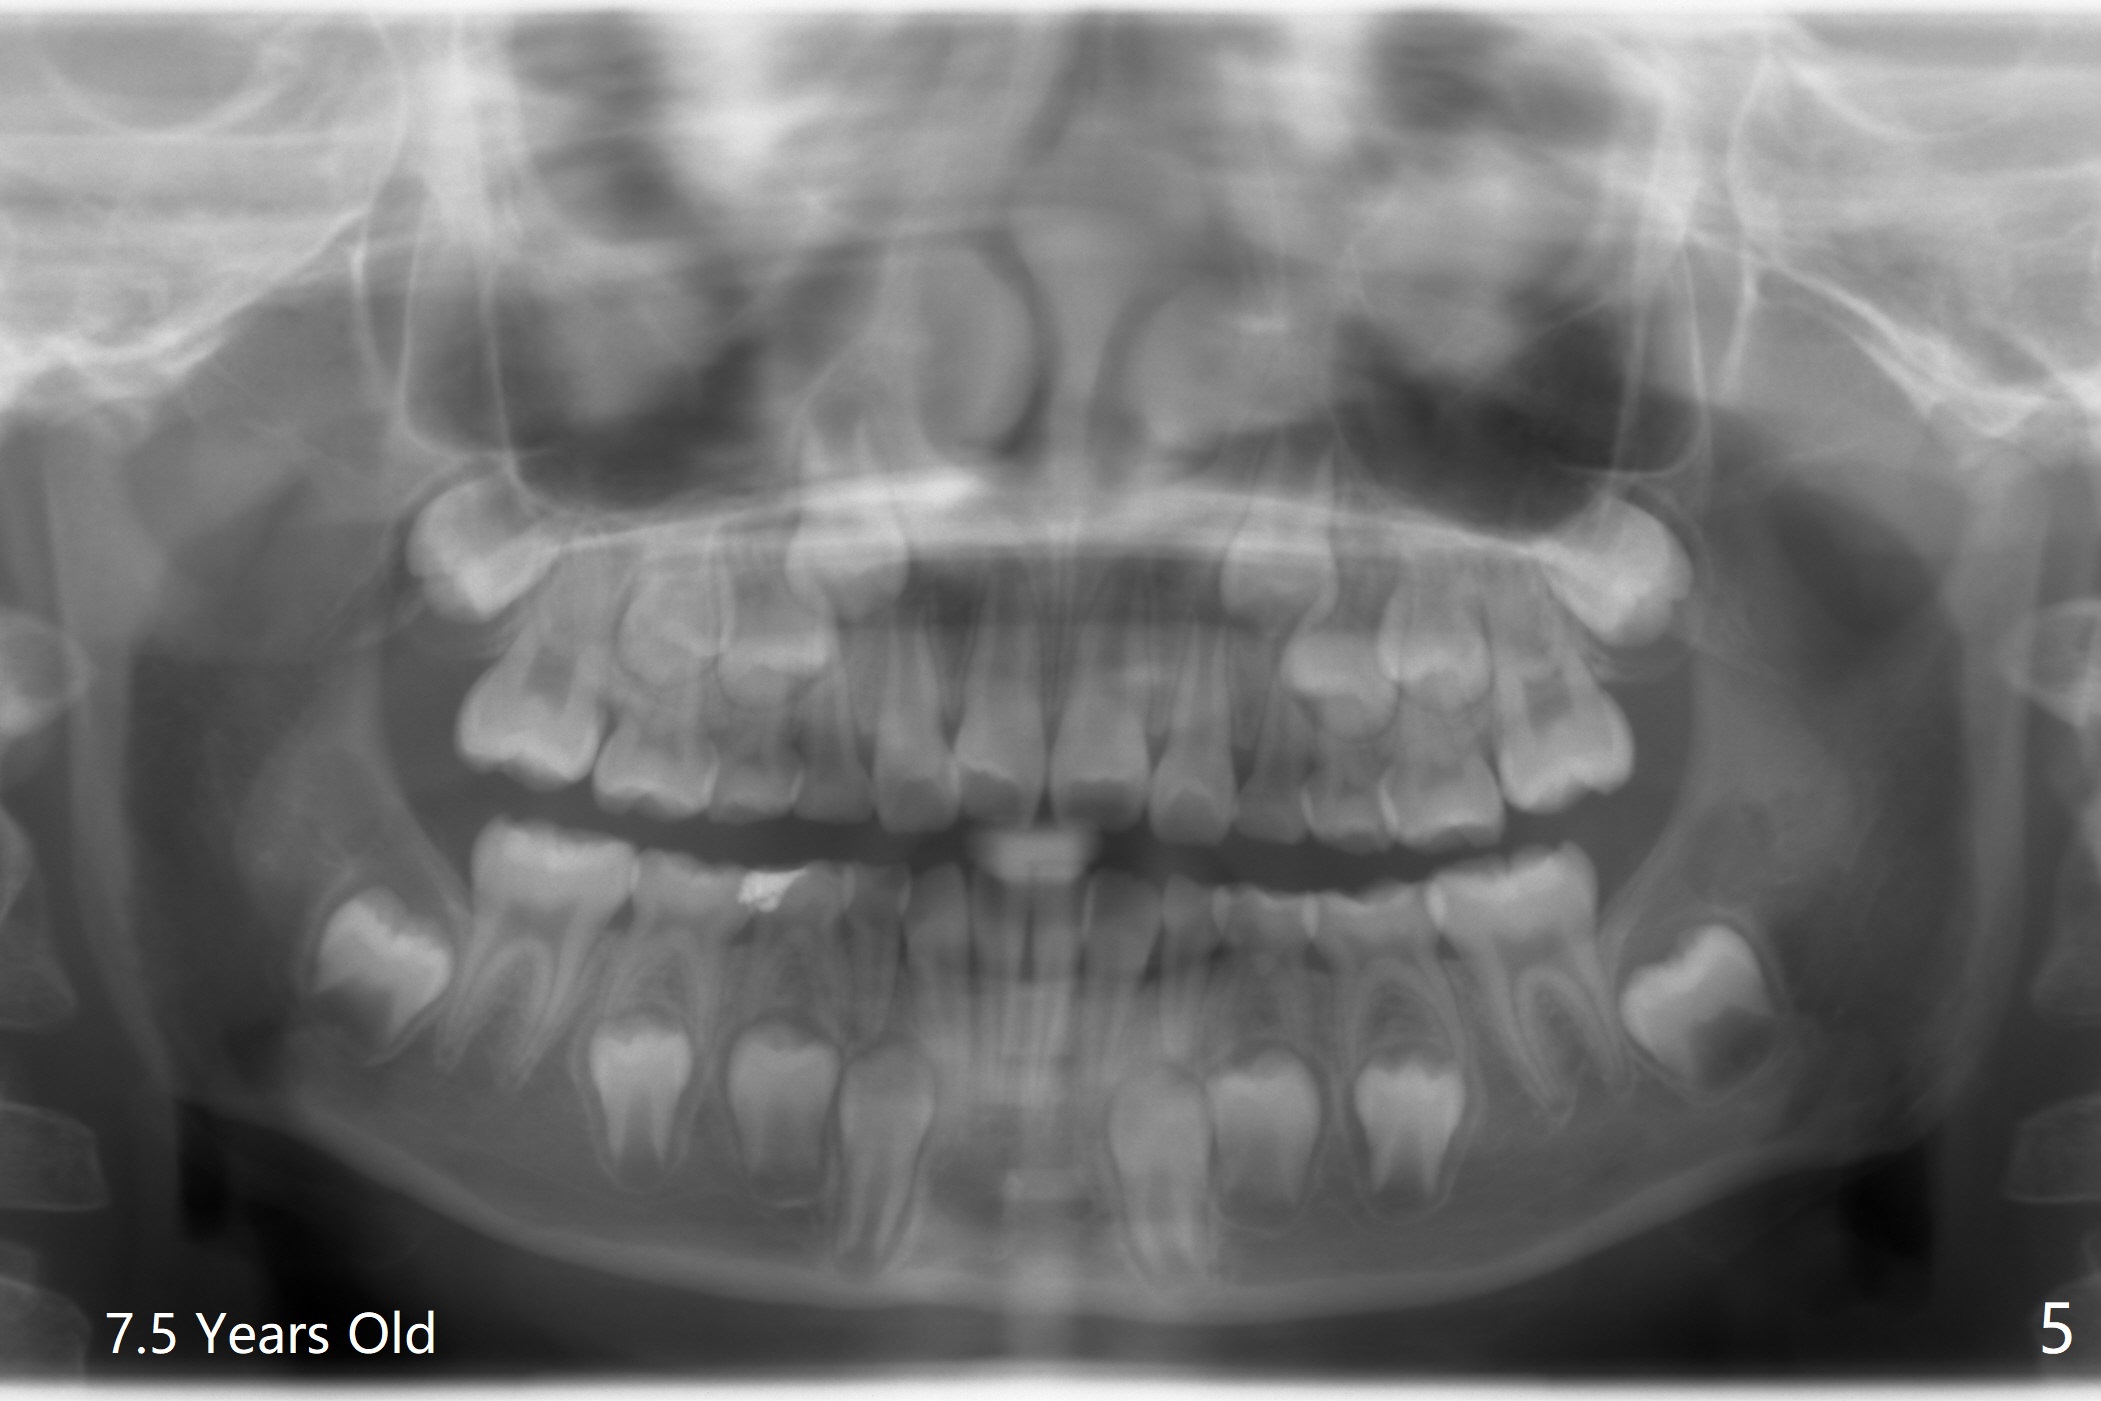

Facial Class I Occlusal Class II

A 12-year-old woman has Class I facial profile (Fig.1-4,12,13) and apparently Class II Division I malocclusion (Fig.6-11). Start Class II retraction as early as possible to take advantage of the upper and lower posterior diastemata (Fig.9,11 (in fact there is no diastema)). LL7 impaction is noted immediately prebanding (Fig.14). Surgical access is pending.